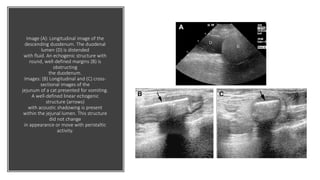

Image (A): Longitudinal image of the

descending duodenum. The duodenal

lumen (D) is distended

with fluid. An echogenic structure with

round, well-defined margins (B) is

obstructing

the duodenum.

Images: (B) Longitudinal and (C) cross-

sectional images of the

jejunum of a cat presented for vomiting.

A well-defined linear echogenic

structure (arrows)

with acoustic shadowing is present

within the jejunal lumen. This structure

did not change

in appearance or move with peristaltic

activity.

Image (A): Longitudinalimage of the descending duodenum. The duodenal lumen (D) is distended with fluid. An echogenic structure with round, well-defined margins (B) is obstructing the duodenum. Images: (B) Longitudinal and (C) cross- sectional images of the jejunum of a cat presented for vomiting. A well-defined linear echogenic structure (arrows) with acoustic shadowing is present within the jejunal lumen. This structure did not change in appearance or move with peristaltic activity.